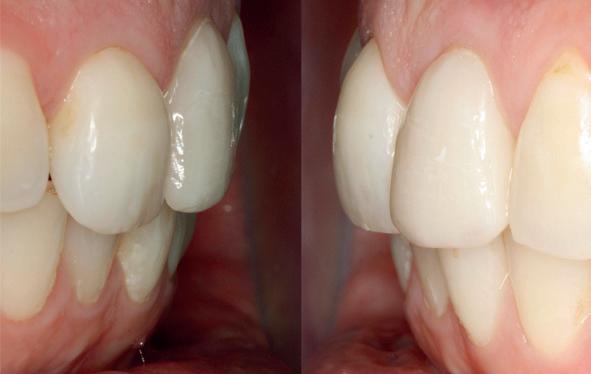

De flap en graft worden met poly-propelene 6.0 hechtingen gefixeerd. De tijdelijke reconstructie wordt herplaatst (foto 17-20).

Na 4-6 weken kan het aangebrachte healing abutment worden vervangen door een tijdelijk abutment. Deze wordt aan de kunststof reconstructie verbonden om zo de gingiva ter plaatse van de 22 te vormen. Zo lijkt het of er geen implantaat maar nog steeds een wortel aanwezig is, wat het esthetisch eindresultaat ten goede zal komen (foto 21-23). Vanaf 4-6 maanden ziet het weefsel er gezond uit. Nu kan met de uiteindelijke restauratiefase worden gestart (foto 24 en 25).

Er wordt een afdruk of een intra-orale scan genomen van de situatie met tijdelijke voorzieningen en de geprepareerde situatie. Ook mag een portretfoto en mondfoto niet ontbreken. Al deze informatie gaat naar het laboratorium zodat de onderstucturen van de restauraties gemaakt kunnen worden (foto 26).

De vier restauraties worden in samenspraak met de ceramist en de patiënt gecustomized. Op dit moment kunnen er nog details worden aangepast om zo het mooiste eindresultaat te behalen.

Bij de evaluatie van deze casus blijkt dat het herstellen van de processen alveolaris ter plaatse van de 22 is gerealiseerd en dat de gingiva qua positie en volume rond de 22 en 23 is verbeterd. Het implantaat is goed ge-osseointegreerd en de gingiva rond het implantaat heeft een natuurlijke vormgeving gekregen. De kronen zijn met moderne technologie en esthetisch hoogwaardig vervaardigd door het Oral Design Center Holland. Met dank aan Eric van der Winden.

De dentale mediaanlijn is rechtop gezet, maar staat niet helemaal gelijk met de faciale mediaan. Echter, mevrouw is functioneel en esthetisch naar tevredenheid afbehandeld (foto 27-30).